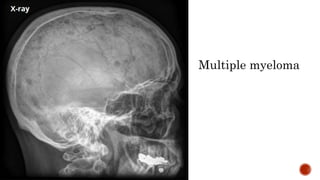

 AP and lateral radiographs of the skull show multiple tiny lucent areas with areas of

sclerosis in between, giving rise to salt and pepper skull appearance.

Multiple myeloma